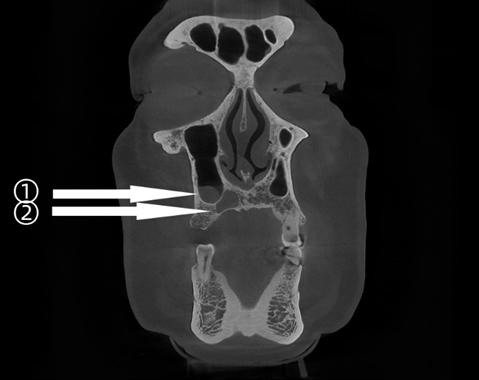

术前检查可见:

13 牙根尖区低密度影,与上颌窦仅一薄骨片;

上颌窦底类圆形高密度影,边界清、骨质无破坏。